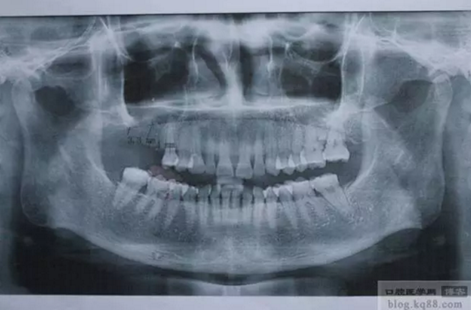

患者:女,49歲,右上6、7缺失,X光顯示右上7骨高度3mm左右,計(jì)劃行上頜竇內(nèi)提升同期植入植體。